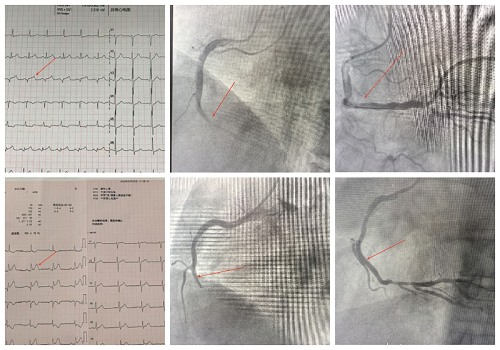

其中,38岁患者的救治过程尤为紧迫。该患者于凌晨02:00突发胸痛,呈压榨样剧痛,位于胸骨中下段后,范围约半拳大小,伴呼吸困难、大汗淋漓,症状持续约10分钟后缓解,但患者未及时就诊,直至清晨自行就诊。接诊医师高度警惕,立即安排检查,首份心电图显示:窦性心律,II、III、aVF导联ST段抬高,提示急性下壁心肌梗死。

时间就是生命,每一分每一秒都关乎患者安危。心血管科徐淑乐主任紧急赶到,查看患者后当即指示立即启动胸痛绿色通道,将患者紧急送往导管室实施介入手术。该患者就诊时无家属、同事陪同,病情紧急不容片刻耽误,医护人员经请示医务处,通过电话视频与患者家属取得联系,详细告知病情及手术风险,在征得家属同意后,为患者实施手术,术中出现多次危急情况,胸痛中心凭借丰富的临床经验与介入技术,沉着应对、精准操作,经过紧张有序的抢救,手术圆满成功,成功开通闭塞的冠状动脉,恢复心肌正常供血,患者胸痛症状缓解,生命体征逐渐平稳,安返CCU病房,目前病情稳定,正在进一步康复中。